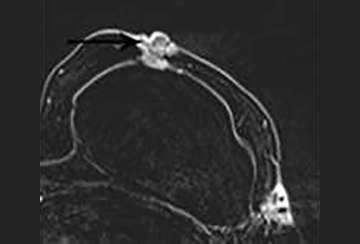

A fluid- or blood-filled cavity following lumpectomy is a normal finding. Seromas are typically T2 hyperintense with smooth, thin rim enhancement (Figure 2a).1 Nodular enhancement greater than 5mm is concerning for residual disease (Figure 2b). A seroma with typical imaging features is a benign finding (BI-RADS 2).

FIGURE 2A: T2-weighted image with fat saturation image. A T2 hyperintense structure is seen in the medial right breast at the site of a lumpectomy. This represents a post-surgical seroma. FIGURE 2B: T1-weighted post contrast image with fat saturation. The seroma cavity demonstrates thin rim-enhancement, a normal finding.